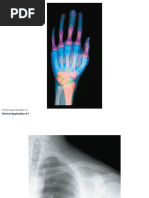

Upper Limb Bones Labeling Guide

The document labels the bones and features of the shoulder girdle (scapula and clavicle), upper arm (humerus), forearm (radius and ulna), and wrist (carpals). It identifies 17 structures on the scapula, 3 on the clavicle, 17 on the humerus, 13 on the radius/ulna, and 8 carpal bones.

Label the diagram below:

Scapula

Clavicle

Humerus

Radius Ulna

Carpal